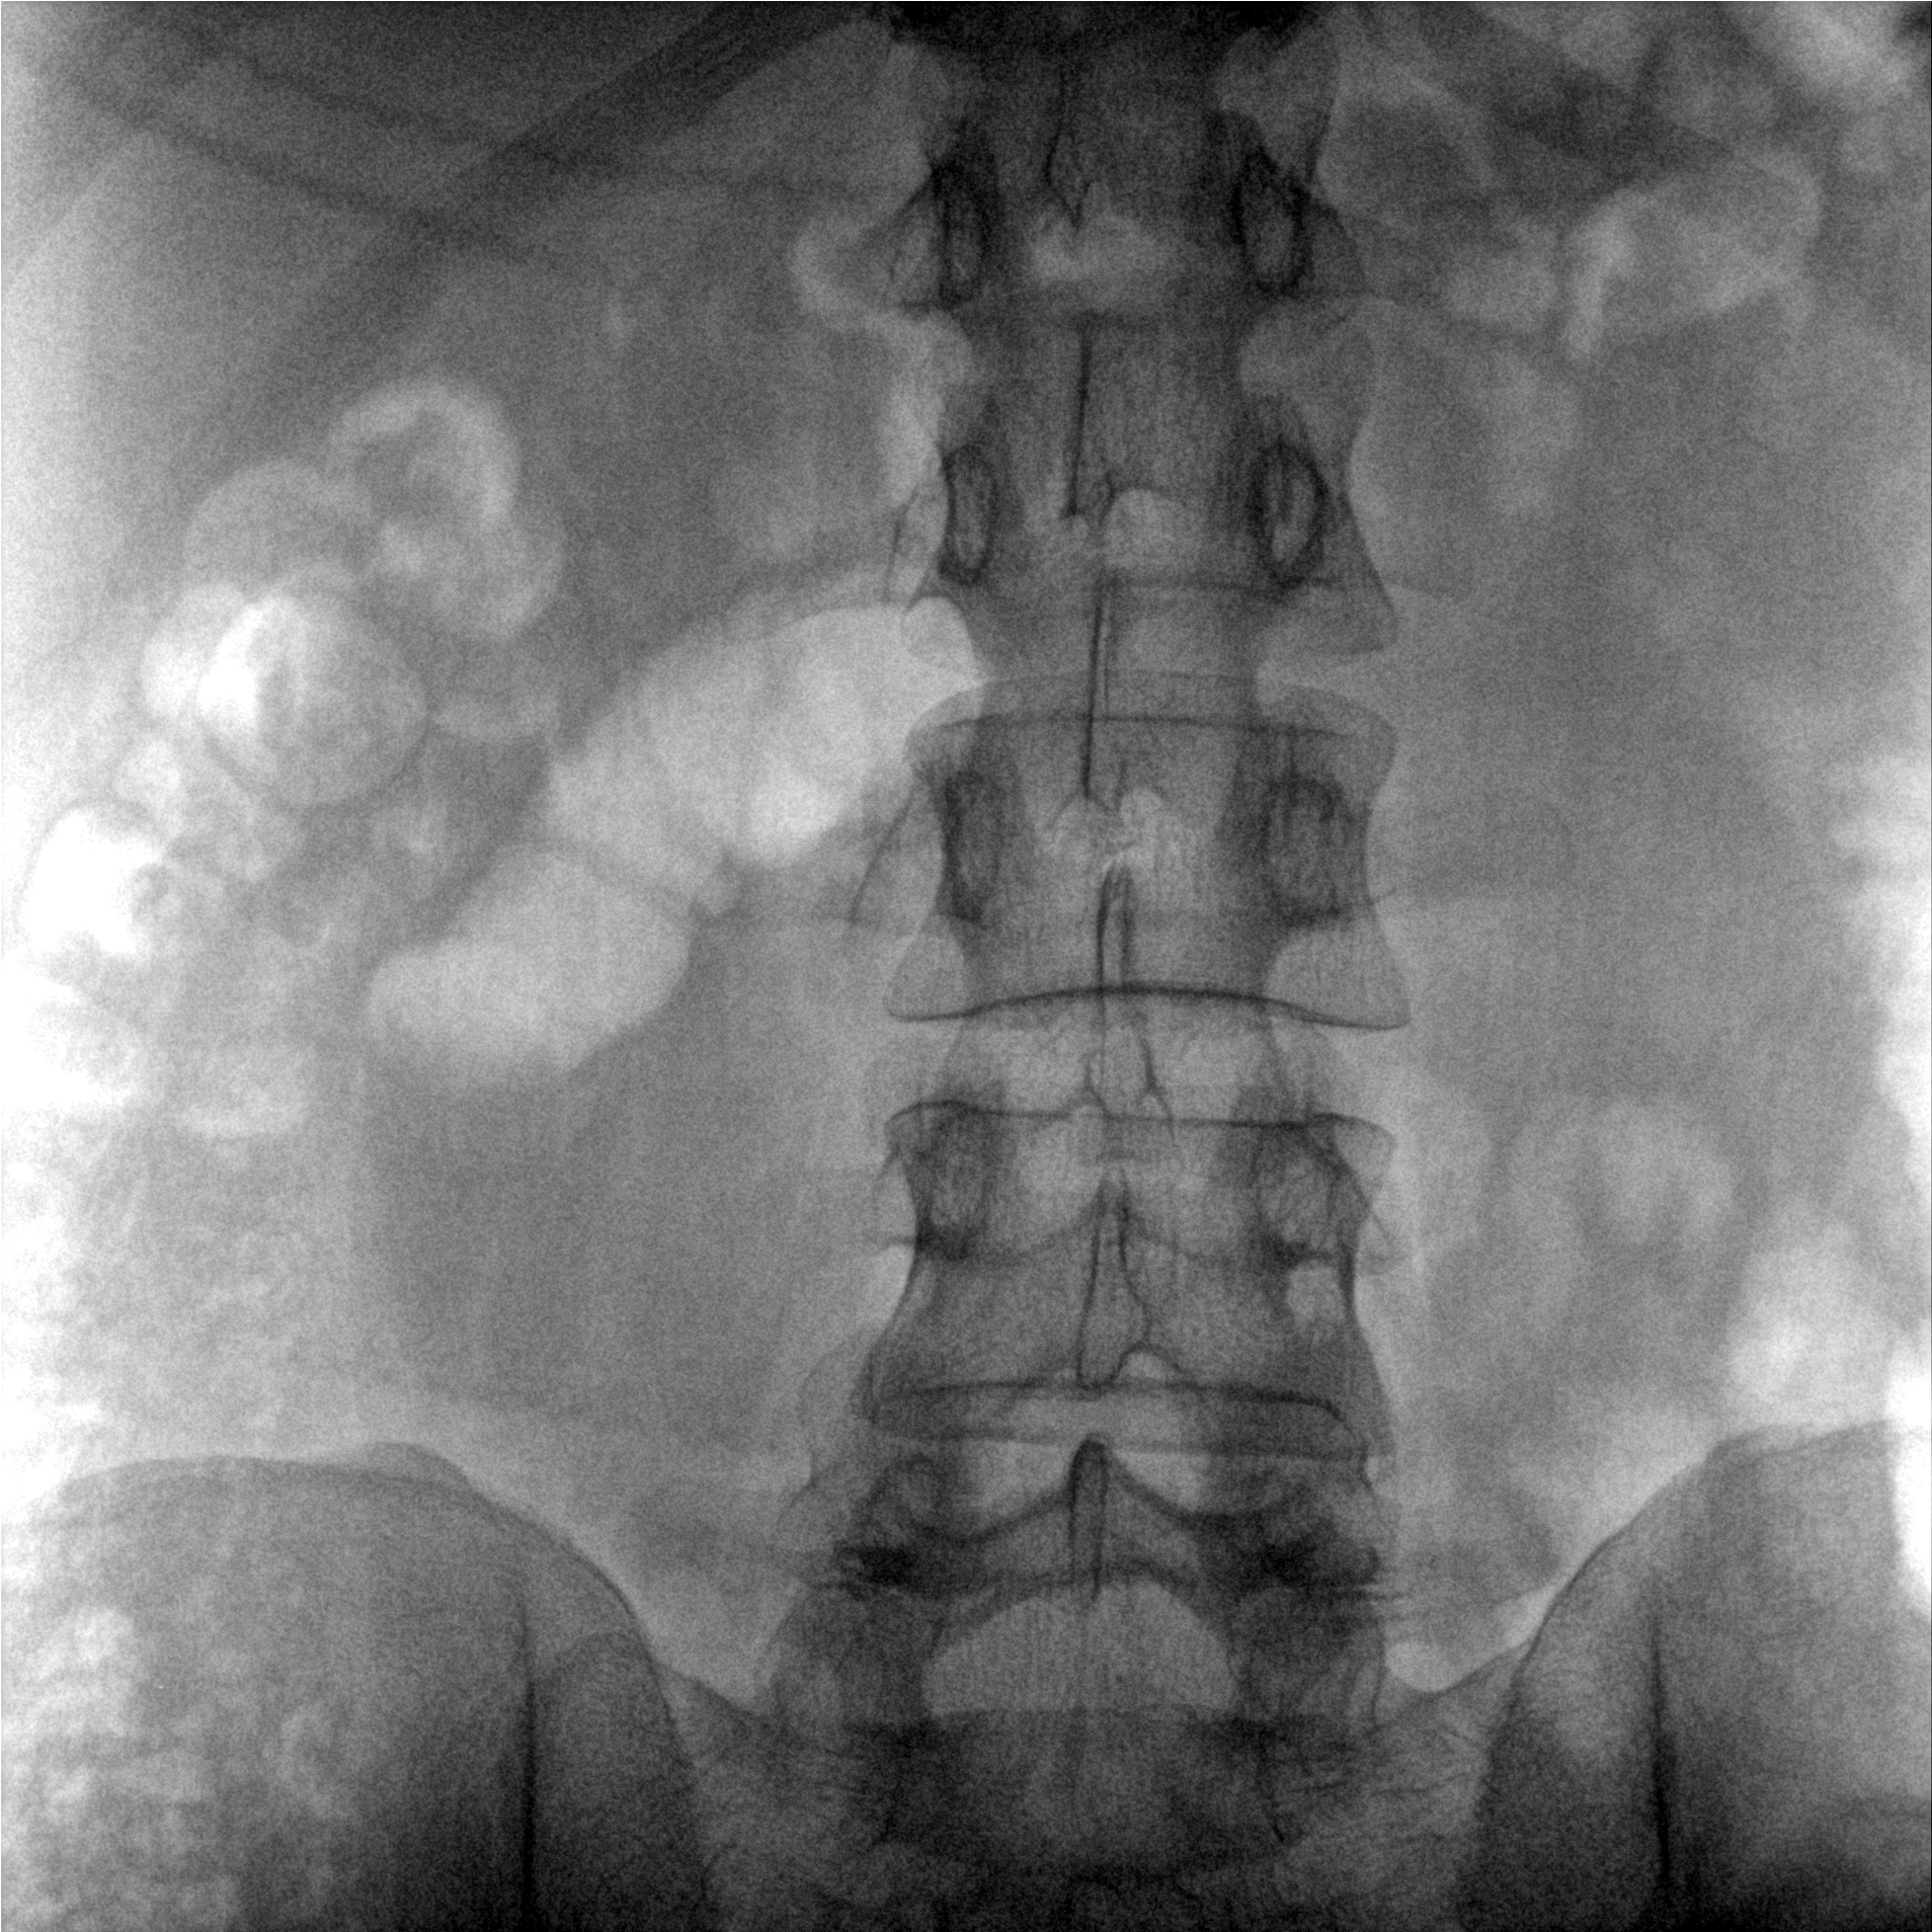

提供更大的術(shù)中三維成像視野,采集更多圖像信息,可一次拍全全段頸椎、全段腰椎、七節(jié)胸椎、雙側(cè)骶髂關(guān)節(jié)、股骨頭及單側(cè)盆骨。